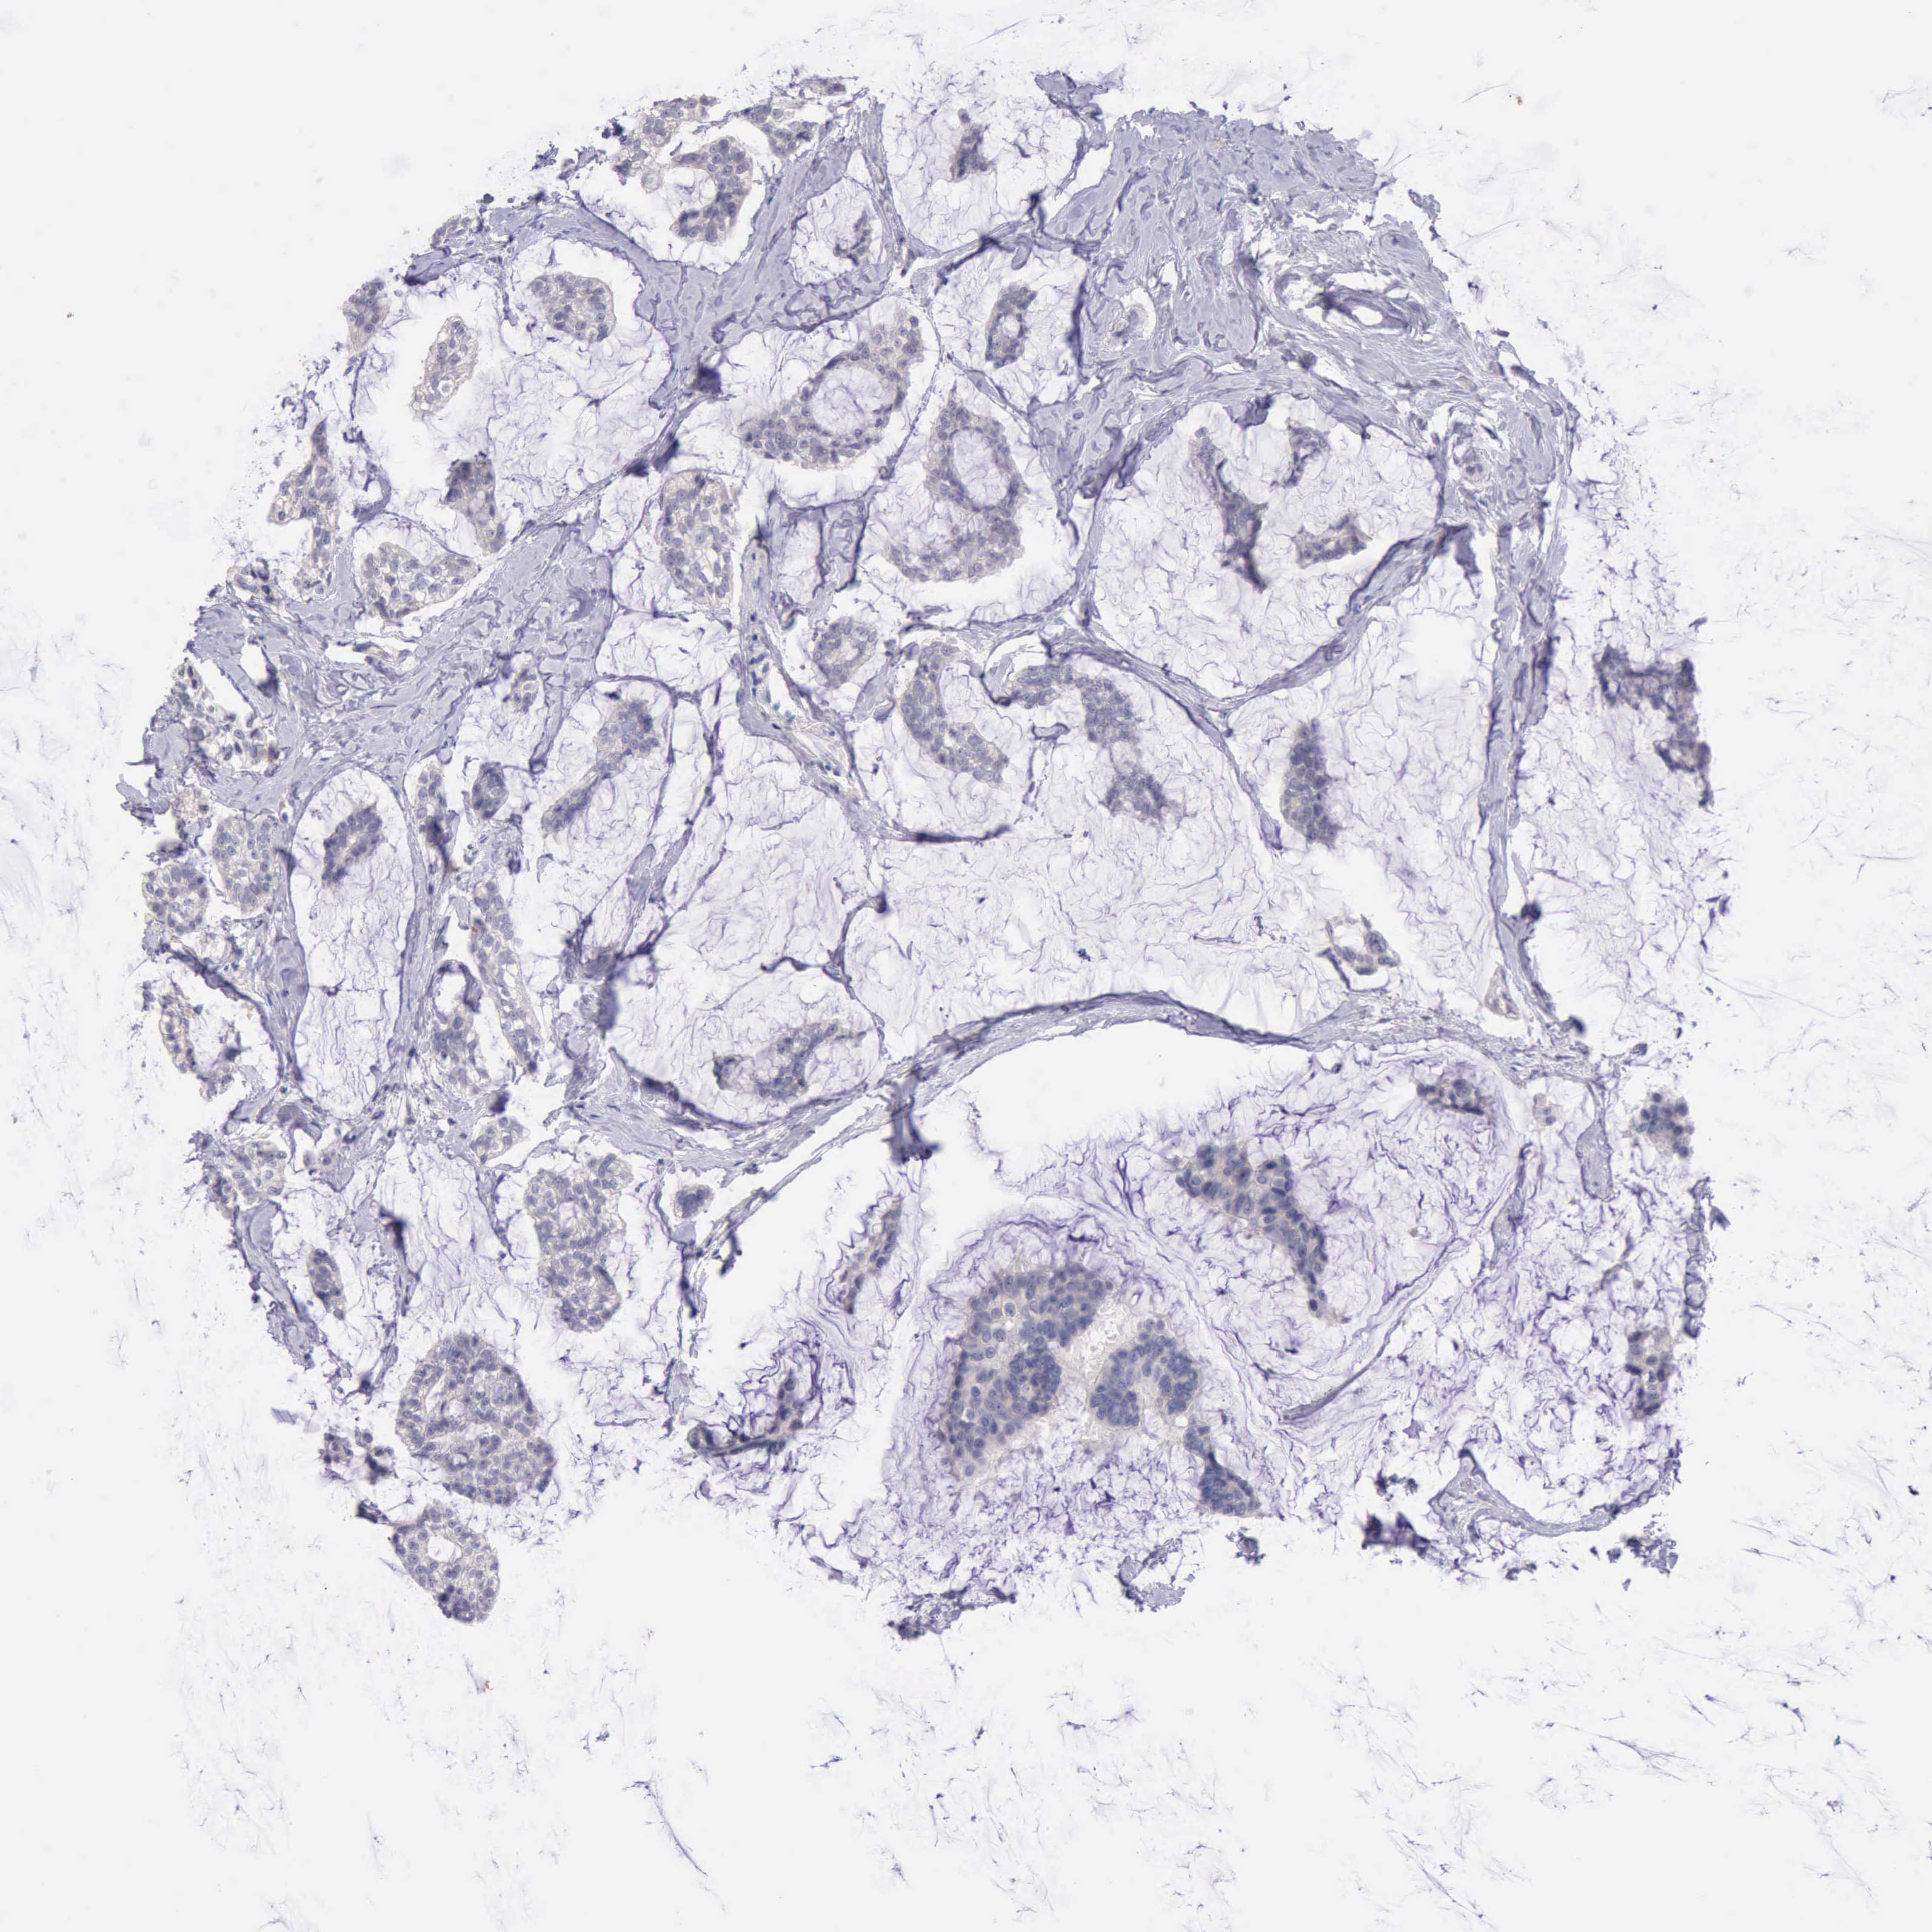

CANCER BREAST CANCER Show tissue menu

BRCA TCGA BRCA VALIDATION PROTEIN EXPRESSION

Breast cancer

Human cancer